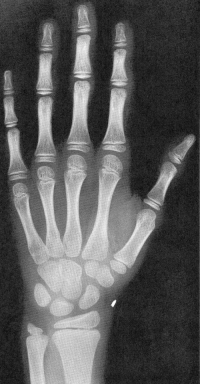

Sexo Masculino

3 meses

idade óssea - 3m